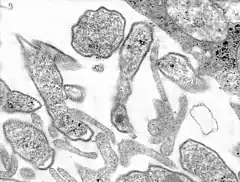

Description de cette image, également commentée ci-après

Coupe fine en miscrocospie électronique

du virus ourlien

Les virions, appelés particules MuV, sont de forme pléomorphe et leur taille varie de 100 à 600 nanomètres de diamètre. Le virus interagit d'abord avec une cellule hôte en se liant à sa surface via le récepteur de la protéine HN, l'acide sialique, qui se lie aux récepteurs de l'acide sialique à la surface des cellules hôtes[2].